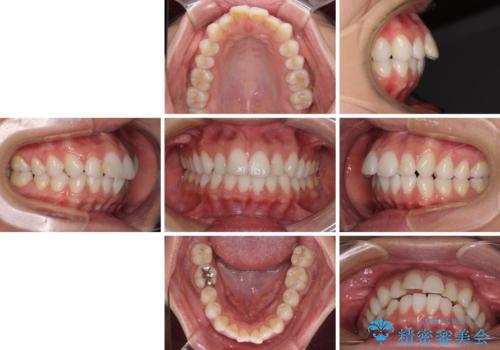

- くちばしのような前歯の突出感を気にして来院された患者様です。

上下左右第一小臼歯4本を抜歯して、積極的に口元を引っ込めるよう、ワイヤー装置にて矯正治療を行うこととしました。

抜歯矯正を行ったことで、顎先のつっぱり感や口元の閉じにくさを解消することができました。